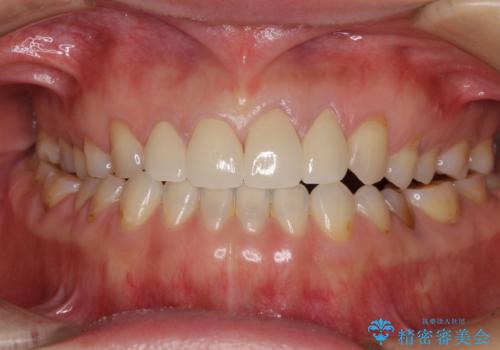

口元への目線ばかりを気にしていた状態から、自然な口元へと変貌し、患者様には大変満足していただきました。